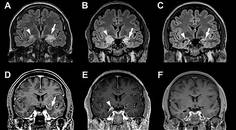

LGI1 Antibody Encephalitis Presenting as Focal Cortical Encephalitis